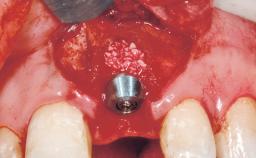

Late Placement of an Implant in a Maxillary Left Central Incisor Site

A 30-year-old female patient had lost tooth 21 and was referred to our clinic for consultation and treatment. Due to advanced apical infection, tooth 21 had been extracted two months earlier at another clinic and an acrylic-resin tooth had been bonded to the adjacent teeth. The patient desired implant treatment to avoid any damage to the adjacent natural teeth. While the patient had no history of any systemic disorder, she was a heavy smoker and exhibited medium to advanced periodontitis in the entire jaw. After the initial treatment to achieve a pocket probing depth of less than 4 mm and no bleeding on probing, a decrease in the height of the papillae mesial and distal to the extraction site and overall gingival recession were observed.